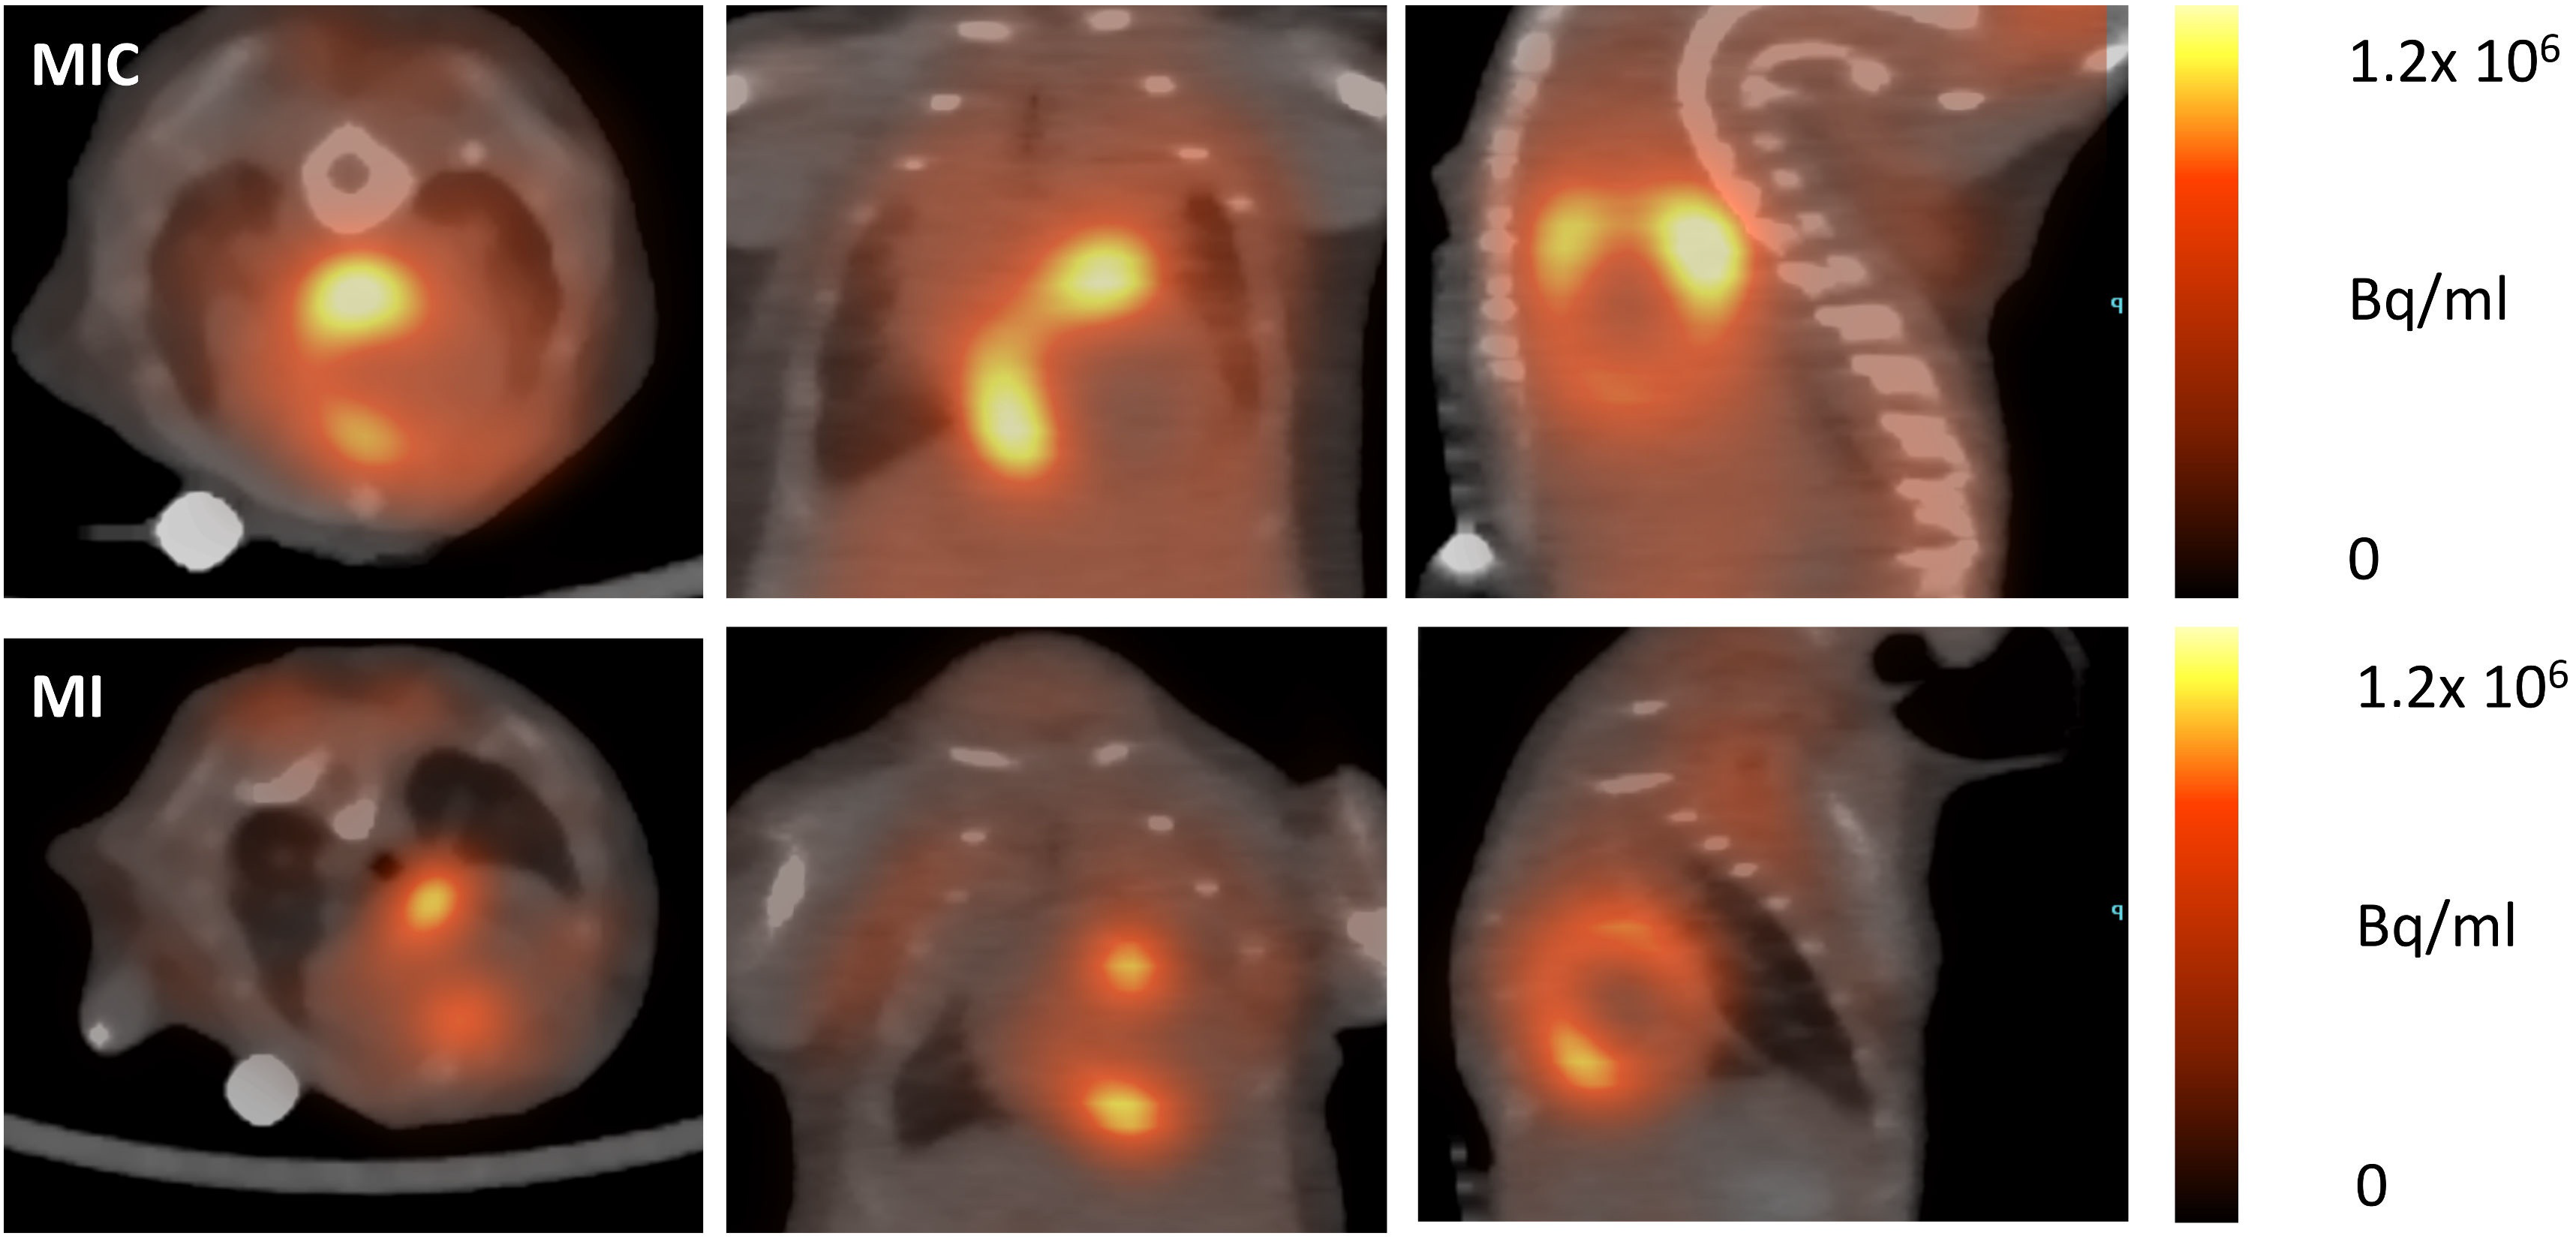

3.3. FDG-Uptake Pattern is Fundamentally Changed by Cell Transplantation